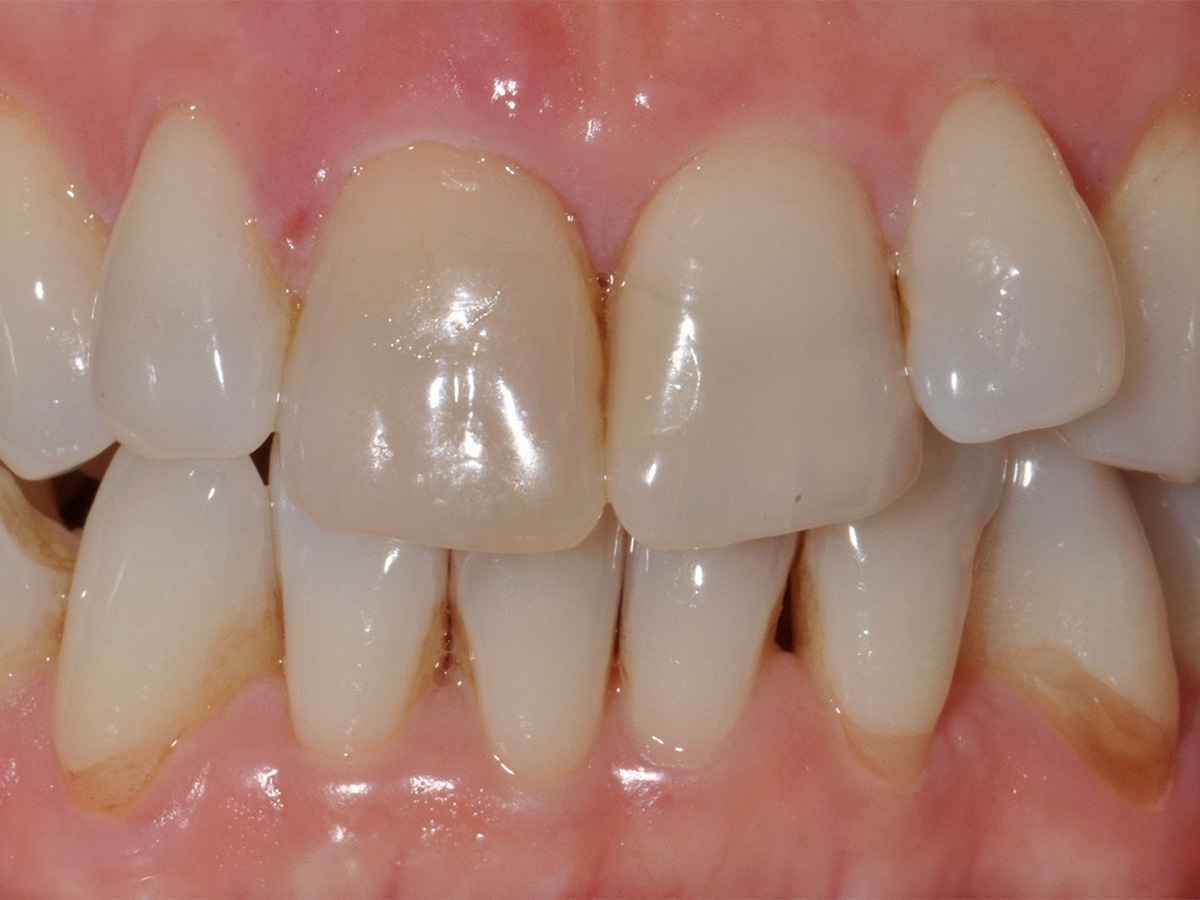

Abbildung 1

Ausgangssituation

Der 38 Jahre alte Patient stellte sich in der Praxis mit Schmerzen in der Oberkieferfront vor. Die klinische Ausgangssituation lässt den Defekt aufgrund der Entzündung nur erahnen (Abb. 1). Der wurzelkanalbehandelte Zahn 11 musste wegen mehrfacher Frakturen extrahiert werden. Die Resorption des Knochens durch die endodontische apikale Läsion und die Entzündung führte zum kompletten Verlust der bukkalen Lamelle (Abb. 2).